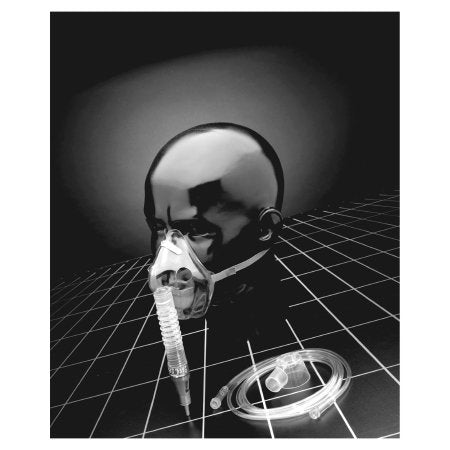

Air Entrainment Mask Percent-O2-Lock Elongated Style Adult One Size Fits Most Adjustable Head Strap

The Percent-O2-Lock Air Entrainment Mask by Sun Med provides precise and adjustable oxygen delivery, making it ideal for both short- and long-term respiratory therapy. Featuring a variable Venturi system, it offers controlled oxygen concentrations ranging from 24% to 50%, ensuring accurate treatment across various patient needs.

Crafted from soft, clear PVC, this elongated style mask includes a trumpet connector, 7-foot oxygen tubing, and an adjustable head strap for maximum comfort and secure placement. Its design makes it especially suitable for edentulous patients or long-term oxygen users.